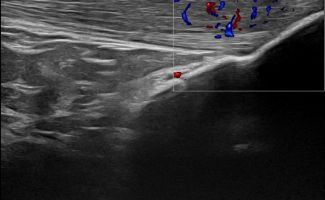

Το Υπερηχογράφημα Γόνατος προσφέρει τη δυνατότητα απεικόνισης παθολογιών στην άρθρωση, τους θυλάκους, τους τένοντες, τους συνδέσμους, τα νεύρα, τα αγγεία και τα μαλακά μόρια της περιοχής του γόνατος.

Η παρουσία συλλογής υγρού, θυλακίτιδας ή υμενίτιδας που ανιχνεύεται με το Υπερηχογράφημα Γόνατος μπορεί να σχετίζεται με ρευματολογική νόσο, όπως:

Αγγεία και Νεύρα Γόνατος

- Θρόμβωση στην Ιγνυακή Φλέβα

- Ανεύρυσμα στην Ιγνυακή Αρτηρία